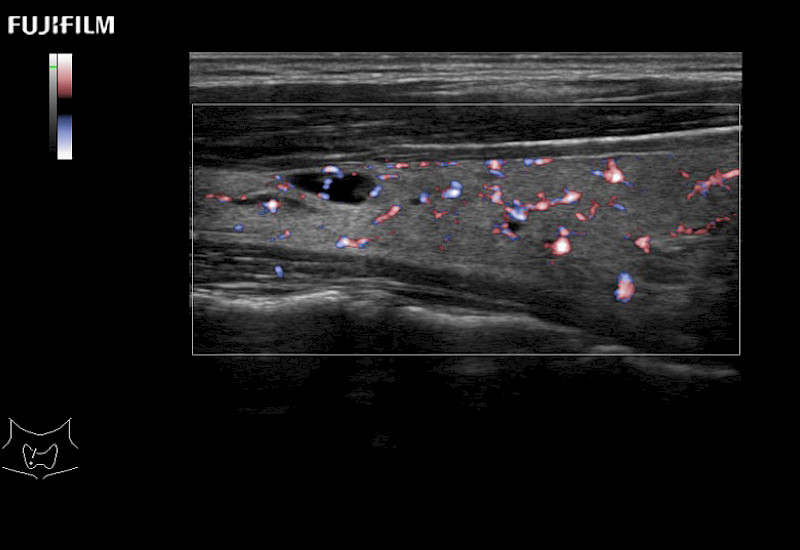

Learn moreFujifilm Healthcare continues to listen to the experts, our neurosurgeons, by developing an ultrasound system specifically designed for the Operating Room.

Guidance is the fundamental purpose for all of our surgical ultrasound technology. Fujifilm Healthcare is committed to designing tools that help neurosurgeons navigate inside the human body and provide the necessary information to immediately make critical surgical decisions.

With the ARIETTA Precision the next level of surgical ultrasound is here.